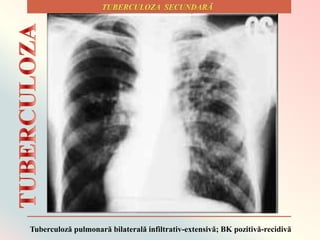

Tuberculoză pulmonară bilaterală infiltrativ-extensivă; BK pozitivă-recidivă

În 15–20% din cazurile active, infecția

se extinde în afara aparatului respirator,

provocând alte tipuri de tuberculoză. Cele

mai frecvente locuri de dezvoltare a

infecției extrapulmonare sunt: pleura

(pleurezie tuberculoasă), sistemul nervos

central (meningită tuberculoasă) și sistemul

limfatic (scrofuloză ganglionară).

Tuberculoza extrapulmonară poate

afecta, printre alte locuri de infectare

posibile, și sistemul uro-genital (tuberculoză

urogenitală), oasele și articulațiile (morbul

lui Pott în cazul localizării la coloana

vertebrală).